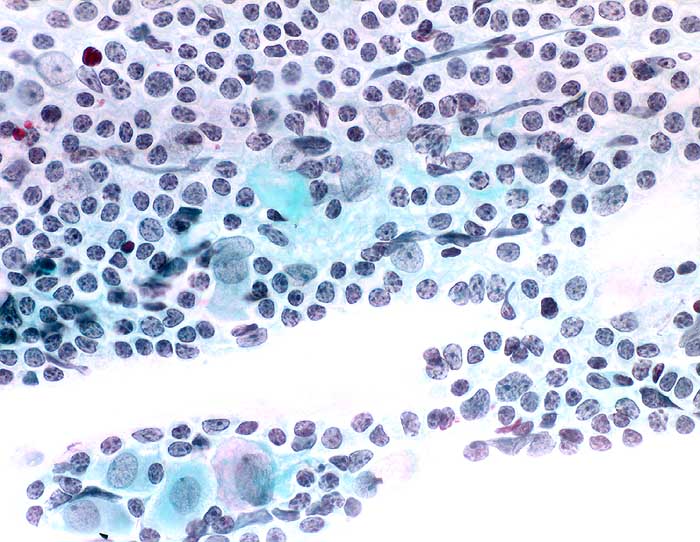

PathoPic ID 6532 - Follikuläre Zervizitis

Follikuläre Zervizitis

Entzündung / Reparatur

Portio

Genitalorgane, weiblich

Portio/Zervixabstrich: dicht gelagerte Keimzentrumszellen.

Vorsorgeuntersuchung

Zytologie

400